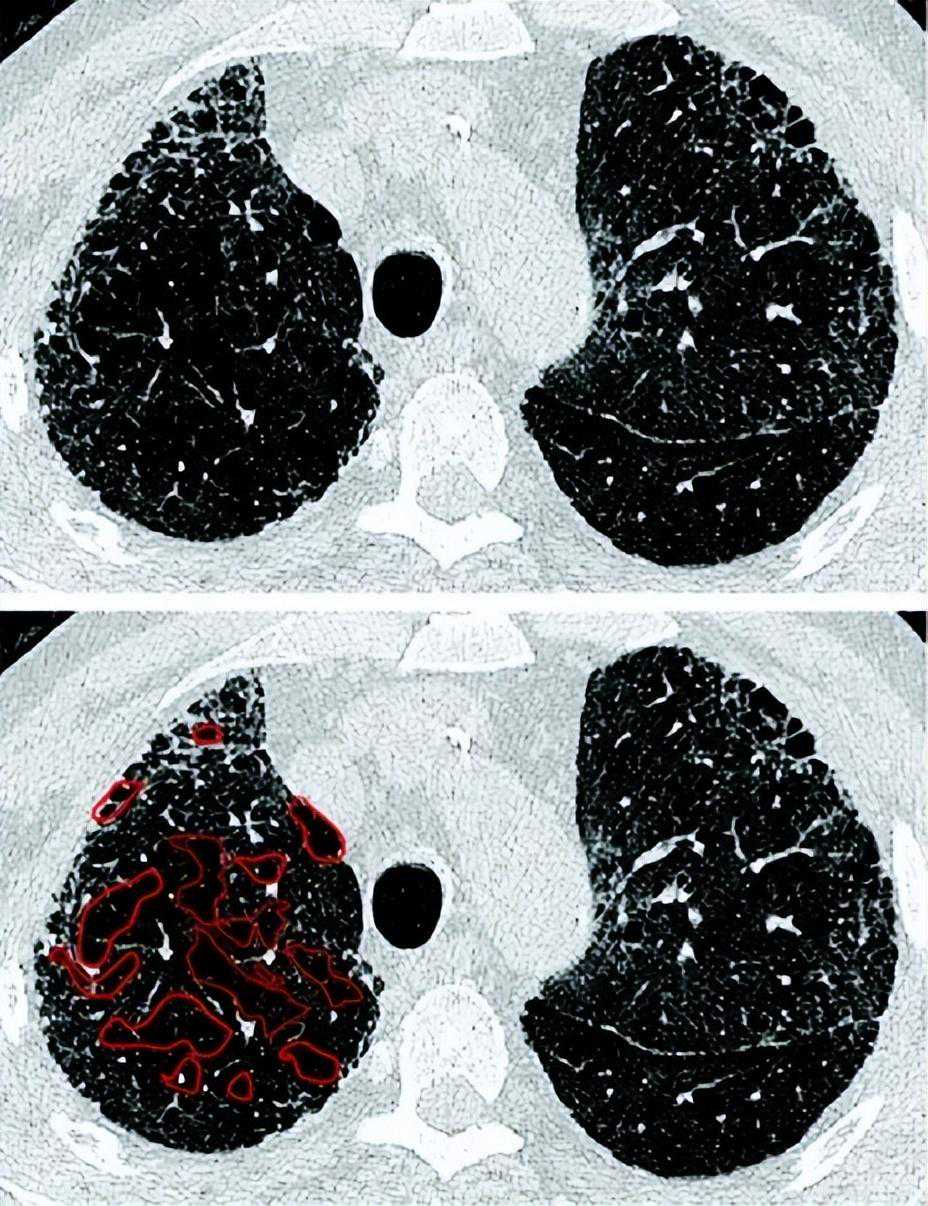

在IPF的背景下,HRCT上的磨砂玻璃样阴影主要代表细小的纤维化,CPFE的纤维化程度是通过将磨玻璃样阴影、网状和蜂窝囊肿加在一起来计算[118,171[。然而,纤维化程度的量化与体积损失相混淆,肺下叶有时严重收缩成很小纤维化区域。然而,当考虑CTD相关的ILD或fHP时,磨玻璃样阴影可能反映炎症而不是纤维化,对于磨玻璃样阴影是否应被视为CPFE纤维化程度的一部分,尚无共识。有人建议,为了符合CPFE定义所要求的“纤维化”因素,磨玻璃样阴影只有在被网状线或牵引性支气管扩张覆盖时才应被量化(图9和E4)[171]。就CPFE中ILD模式的量化达成一致,对于未来协调研究解释以及就首选的视觉纤维化量化方法(体积叶评分与五或六级HRCT切片评分;纤维化程度的分类与连续评分)达成一致将是重要的。

图9:肺气肿视觉评分。特发性肺纤维化和肺气肿患者上叶的轴向切面(上)。肺气肿通过肺叶不规则分布,使视觉量化困难。目视合并肺气肿病灶(下)并估计其组成的肺叶的比例(即,50%,33%,25%,20%,15%,10%或5%)可以简化复杂性病例的定量(见在线补充)。